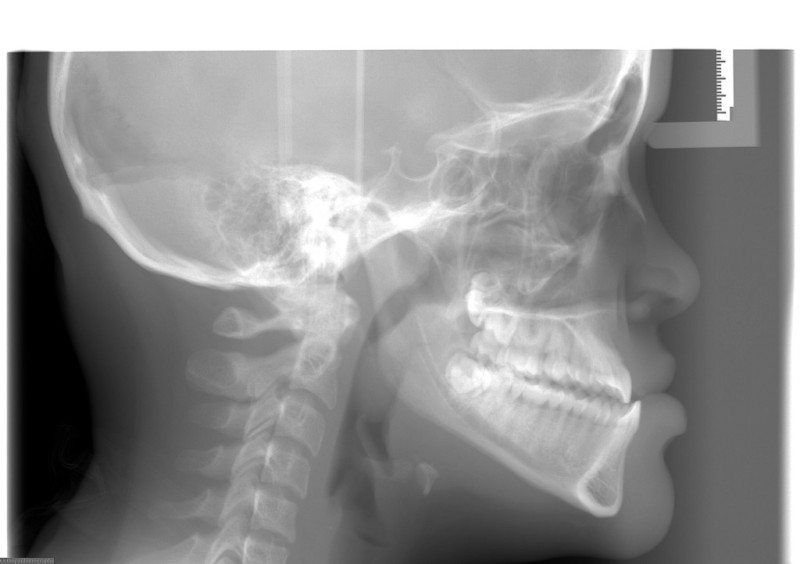

Pretreatment - Patient on Presentation

After Orthodontic Setup - Presurgical